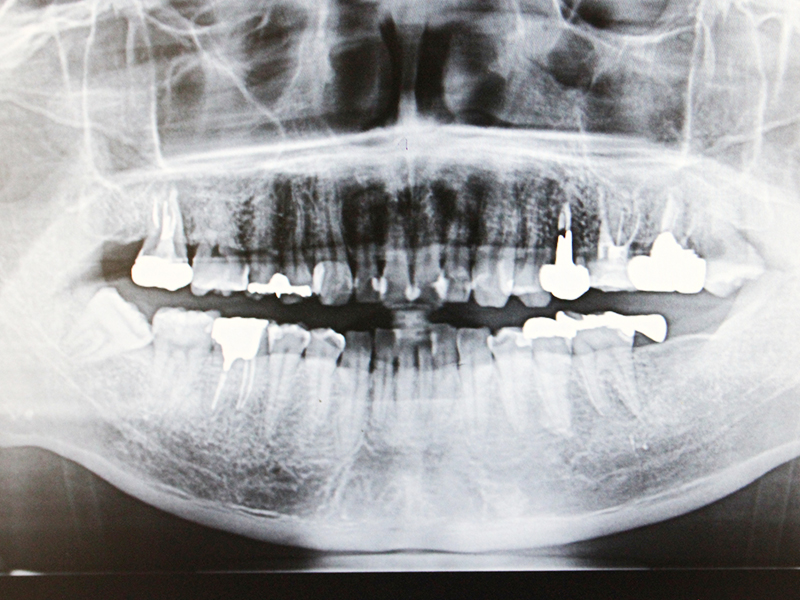

2008年、第一大臼歯の歯根破折を主訴に来院された。

サイナスリフト後にインプラント埋入。

左は術前のレントゲン写真。中央、右は2024年、術後約16年後のレントゲン写真と口腔内写真。

1枚目上、奥歯2本欠損でインプラント治療を希望された。サイナスリフト後、インプラント埋入。

2枚目、術後約10年経過。レントゲン的にも経過良好です。

上顎全顎、左下欠損部、インプラント治療希望で来院。

左上上顎洞にサイナスリフトを行いました。

下顎前歯部は矯正治療にて歯列を回復しました。

術後15年、経過良好です。